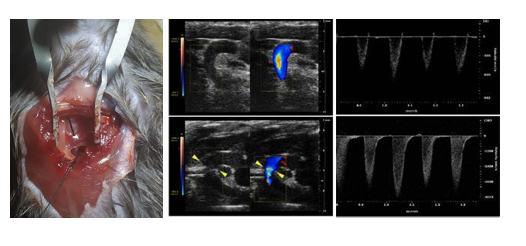

主動脈弓縮窄模型(transverse aortic constriction, TAC)最早由Rockman等于1991年正式建立,是慢性心室肥大常用的疾病模型,用于模擬高血壓或室內壓增高而引起的肥厚性心肌病、心衰。TAC術后,主動脈弓部定量的縮窄引起主動脈血流受阻,左心室壓力負荷增加,誘發(fā)了左心室的心室肥厚,早期以向心性肥厚為主,心功能可有效代償,隨著時間的延續(xù),進行性發(fā)展為心腔的擴張,最終發(fā)展為心力衰竭。

根據(jù)動物品系、基因型和手術縮窄程度的不同,心室肥厚和心衰的進程不同。TAC術后1周可發(fā)展為顯著性的心室肥厚,2-3周發(fā)展為心力衰竭。